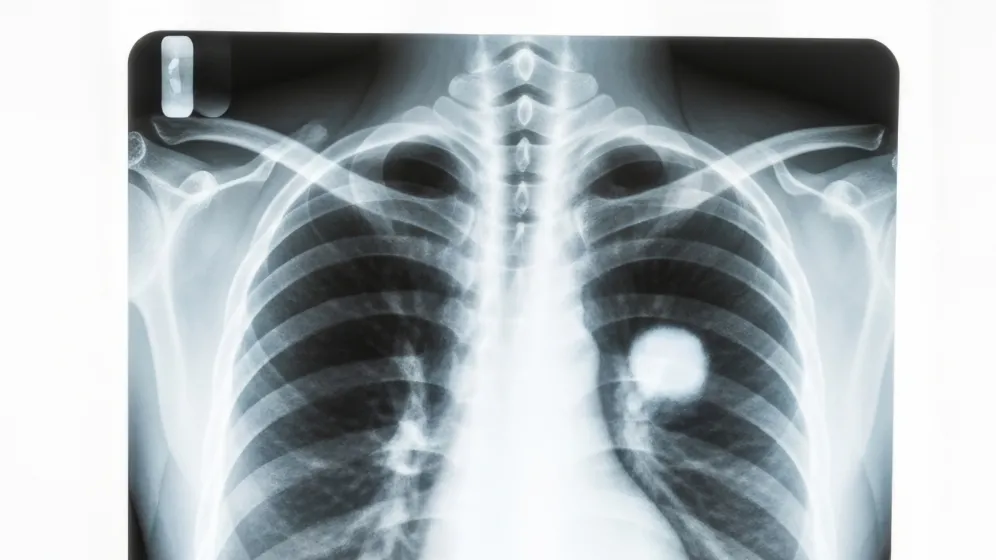

Luki w diagnostyce raka płuca

Szybka diagnoza raka płuca jest kluczem do dobrania odpowiedniej metody leczenia. Nowoczesnych terapii wciąż przybywa, ale w wielu przypadkach rozciągnięta w czasie diagnostyka zmniejsza do nich dostęp.

Epidemiologia raka płuca

Mimo że w ostatnich latach nie obserwuje się znaczącego wzrostu zachorowań na raka płuca (rocznie to 21-23 tys. nowych przypadków), to u kobiet stał się najczęściej występującym nowotworem. Przesunął się w statystykach ponad raka piersi. W Polsce u ponad połowy pacjentów wciąż rozpoznaje się go w zaawansowanym stadium, gdy rokowania są zdecydowanie gorsze.

„To, co jest jeszcze istotne w tym obrazie epidemiologicznym, to że wśród chorych, którzy są rozpoznawani w stadium uogólnienia, u istotnej części z nich proces diagnostyczny trwa tak długo, że przestają być kandydatami do jakiegokolwiek leczenia przyczynowego z powodu bardzo znacznego zaawansowania, chorób współwystępujących” – zaznacza prof. Krzakowski.